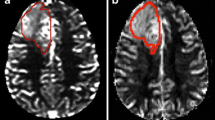

Semi-quantitative ‘hot spot’ analysis

‘Hot spot’ and VOI processing of dynamic susceptibility contrast (DSC) images of two glioblastoma lesions. The white circular region of interest (ROI) markers seen in the DSC-PW (left) and post-contrast T1-weighted (right) sequences in the ‘hot spot’ column serve as an example of ROI placement using the ‘hot spot’ methodology commonly used in clinical practice. The area of slightly higher CBV measured in the perceived ‘hot spot’ correlates to a part of the enhancing region. In the VOI column the automatically selected lesion volume of interest in the same two patients can be seen in the post-contrast T1-weighted sequence (left), the respective lesion perfusion can be seen in the DSC-PW sequence (right). The contrast-enhancing region illustrated in A turned out to be tumor progression, while the lesions in B involuted over time and was therefore considered a treatment related abnormality

Semi-automatic VOI analysis

A workstation equipped with OsiriX MD (Version 12.0; http://www.osirix-viewer.com) and a commercially available plug-in (IB Neuro; Imaging Biometrics, Elm Grove, Wisconsin), which uses a leakage-correction algorithm to process perfusion data and calculate perfusion maps [15, 18, 19] was used for this analysis. For semiautomated image analysis, we used IB Rad Tech (Imaging Biometrics, Elm Grove, Wisconsin), which is a workflow engine that plots rCBV maps in semi-automatically defined volumes of interest [18, 20, 21]. A standardisation of the cerebral blood volume map was automatically performed by IB Rad Tech using a standardisation protocol developed by Bedekar et al. [22]. To visualise the T1-enhancing lesion more clearly IB Rad Tech first subtracted the intensities of the standardized pre-contrast T1 from the standardized post-contrast T1, creating a ΔT1-weighted sequence. This was followed by the semi-automatic selection of defined volumes of interest, which concerns the manual drawing of an ROI around the ΔT1-weighted area of interest, after which the protocol automatically selected the voxels that showed contrast enhancement in the drawn ROI, thus creating a complete selection of the volume of interest as seen in Fig. 1. Mean and maximum rCBV values and volumetric parameters of the contrast enhancing VOIs were automatically generated by the software package for each lesion. This semi-automatic analysis was done by a single radiology resident (D.H.) with profound experience using the software. This approach was chosen because the standardization protocol of the software package is known to produce highly reproducible rCBV values as it does not rely on manual reference placement and compensates for variability in acquisition differences [22,23,24]. Secondly, the semi-automatic VOI selection based on contrast-enhancing pixels in the ΔT1-weighted sequence left little room for inter-operator variability, as it is only susceptible to other contrast enhancing artifacts such as blood vessels, which trained radiologists should be able to identify.